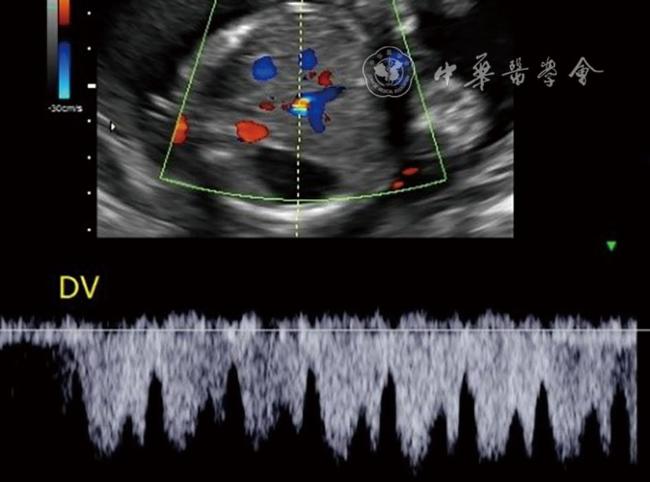

孕妇26岁,自然受孕,孕1产0,单胎妊娠,妊娠期合并甲状腺功能减退及糖尿病。孕12周胎儿颈项透明层厚度检查正常,静脉导管频谱正常。唐氏筛查、无创染色体检测均正常。孕22周6 d进行常规胎儿Ⅲ级超声检查,发现脐血管数目异常,脐带内有4条血管,2条脐动脉合并2条脐静脉(图1)。腹部脐带血管入口处见2条脐静脉进入腹壁,进入腹壁后分别向胎儿腹部左右侧走行,右侧走行血管汇入右侧门静脉,左侧走行血管汇入左侧门静脉(图2)。左侧门静脉向后发出静脉导管,静脉导管汇入下腔静脉,于静脉导管处可测得静脉导管频谱(图3)。胎儿脐静脉、门静脉及其分支、肝静脉之间未见血管分流。超声提示:胎儿双脐静脉,持续性右脐静脉合并左脐静脉。于孕40周3 d剖宫产出生1男婴,体质量为3550 g,Apgar评分为9~10分。新生儿肝功能、心脏超声、黄疸值等检查结果均正常。出生后1 d超声检查,腹内段脐静脉及静脉导管未闭合,超声所见与产前检查相同。

图3 胎儿静脉导管(DV)超声血流频谱图像